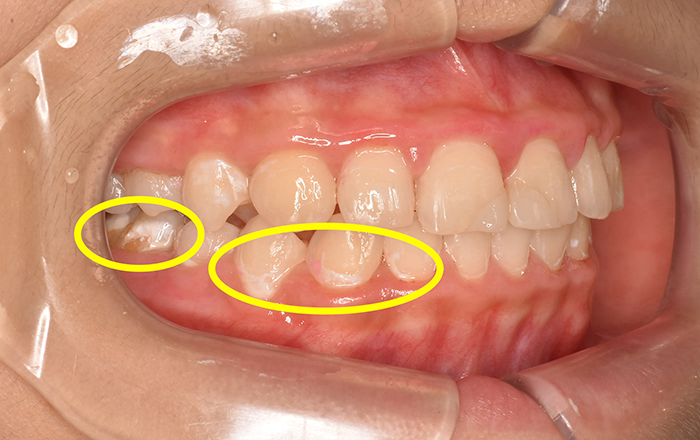

この歯にできる白い斑点の模様のことをホワイトスポットと呼びます。

1つ目の原因は、初期段階の虫歯です。

歯ブラシが上手にできず歯にプラークという細菌が残っていると、歯の表面からミネラル分が溶け出して、“脱灰”を起こします。

それを何回も繰り返していると、歯は徐々に白く濁っていき、見た目でもわかるようになります。しかし、この状態はまだ削って治療しなければいけない段階ではなく、歯ブラシを頑張ってしっかりと細菌をとったり、フッ素を活用することによって、現状維持をすることができます。

逆を言うと、そのまま歯ブラシができていない状態が続いてしまうと、白い斑点のところが茶色く、黒くなり、穴も開いてしまい、治療をしなければいけない虫歯となります。

2つ目の原因は…エナメル質形成不全症と言われるものです。

簡単に言うと、エナメル質形成不全は、歯の表面にあるエナメル質がうまく形成できていない状態です。これは遺伝で起こったり、歯の発育段階のときに外傷を受けたり、乳歯に大きな虫歯ができた影響が永久歯にまでおよび、エナメル質形成不全が起きることがあります。

エナメル質形成不全の場所は虫歯にもなりやすい上に、虫歯の進行も早いです。